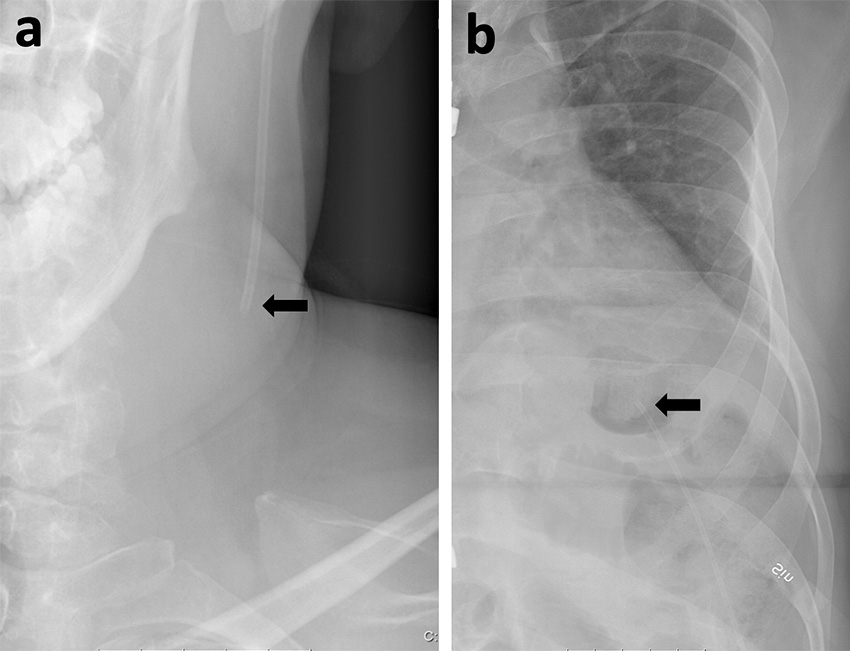

Shuntöversikt som påvisar shuntavbrott på halsen (a) samt torax (b).